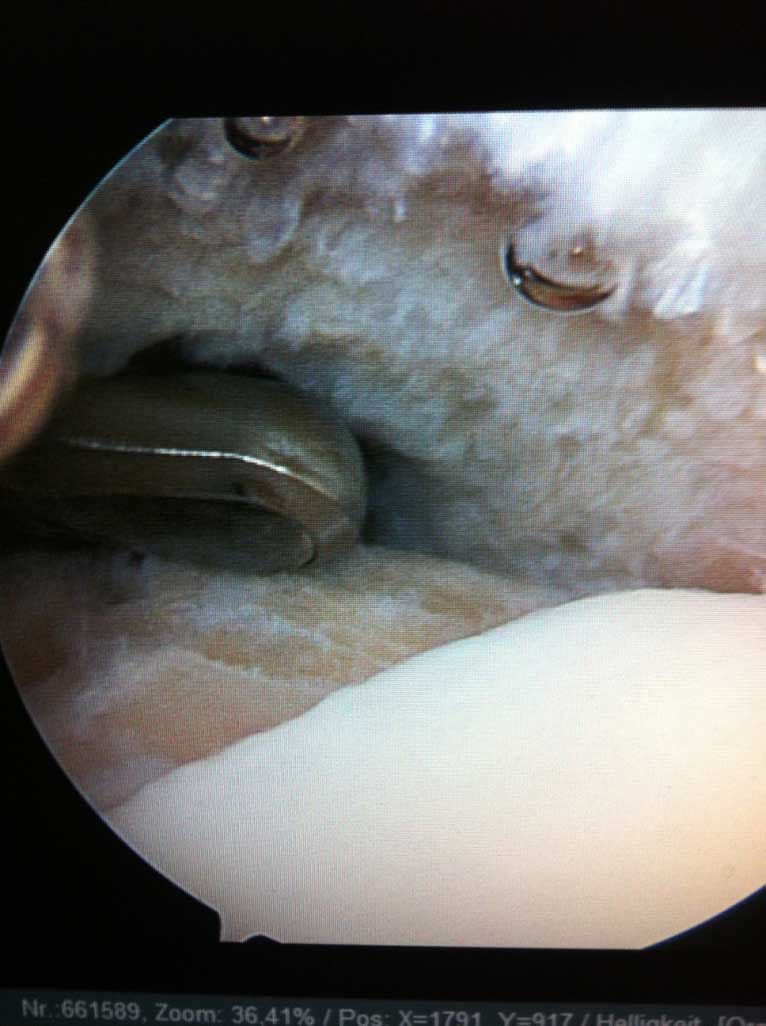

Je nach Alter, Verletzungsmuster, Anzahl der Luxationsereingnisse und weiteren Faktoren, wird eine schulterstabilisierende Operation indiziert und empfohlen. Diese führen wir ebenfalls ausschliesslich arthroskopisch

(Schüsselloch Operation) durch. Innerhalb von 15 - 30 min wird dabei der knorpelige Ring (s.g. Labrum) auf den knöchernen Pfannenrand mit speziellen Anker und Fäden wieder zurück befestigt.

Die operationsbedürftigen Verletzungen versorgen wir mit kleinen Implantaten arthroskopisch. Im Gegensatz zu Versorgung mit Platten oder Drähte ist bei unserem arthroskopischen Verfahren eine spätere Metallentfernung (2. Eingriff) nicht notwendig.